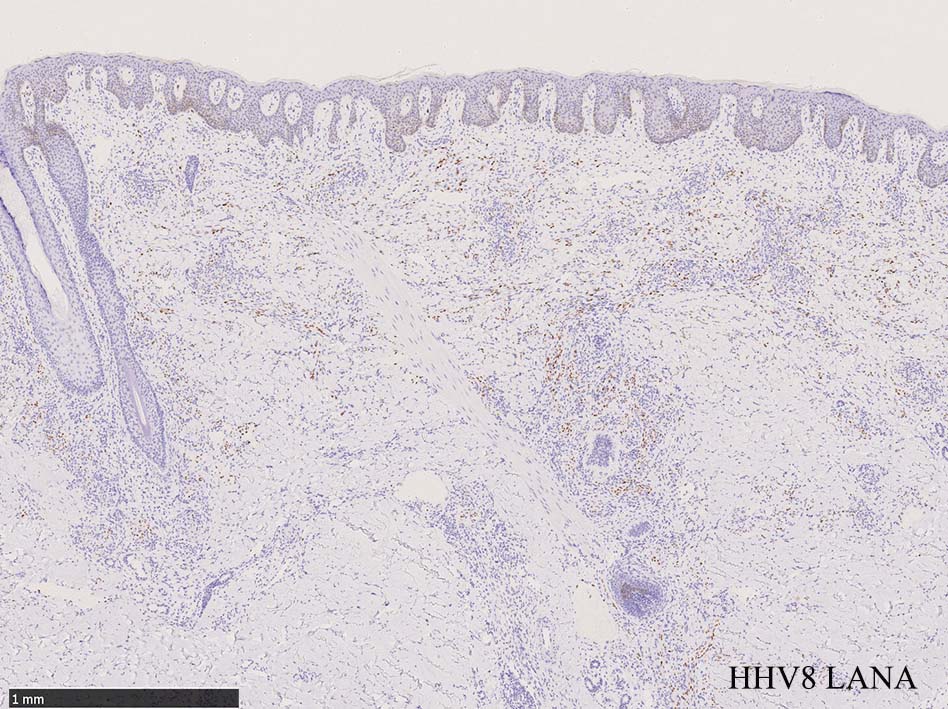

免疫染色, 分子病理学的検査

増生細胞はCd31, CD34, Factor Ⅷ, D2-40などが陽性を示す.

HHV-8の潜伏期関連抗原(HHV-8 Latency-associated nuclear antigen: HHV-8 LANA)が市販されており, 核が点状に染色される陽性所見がKaposi肉腫の確定診断に必須となっている.

組織からのPCRによるHHV-8の検出も診断に有用である.